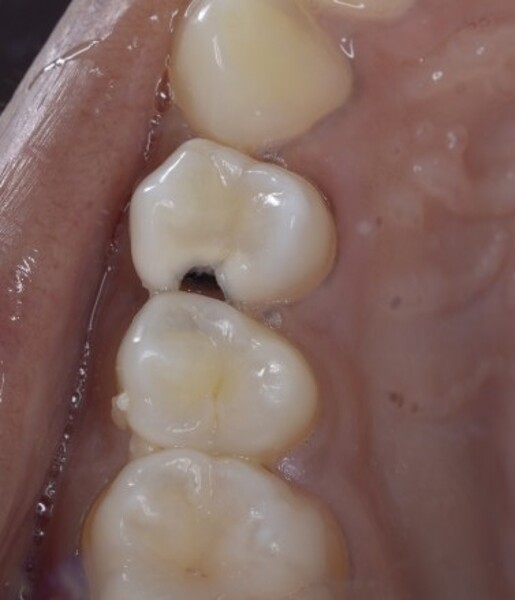

Predictable posterior restorations